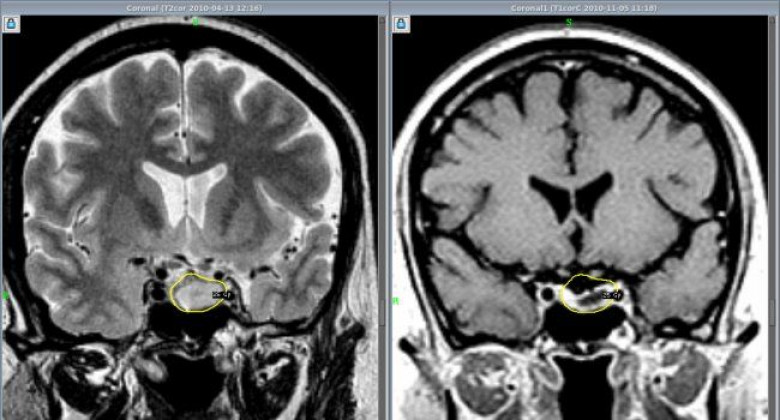

Аденома гипофиза – это доброкачественное новообразование, которое может крайне негативно сказываться на качестве жизни, вызывая нарушения со стороны эндокринной системы, а также нарушения зрения.

До недавних пор такие новообразования в МЦ «Астхик» удаляли с применением хирургического микроскопа. Теперь в медцентре внедряют и другой метод удаления аденом гипофиза – с помощью эндоскопа. Этот метод до недавних пор в Армении не применялся, и обучать ему специалистов в рамках одного из проектов благотворительного фонда «Вива» будет известный нейрохирург Вилен Азизян (Россия). В медицинском центре «Астхик» он уже провел три операции по удалению аденом гипофиза. Ассистировали ему армянские специалисты, которые в дальнейшем научатся проводить такие операции самостоятельно.

Аветис Киракосян, руководитель отделения нейрохирургии МЦ «Астхик», рассказал журналистам о том, что для внедрения эндоскопического метода удаления опухолей гипофиза был выбран медцентр «Астхик», так как материально-техническая база центра соответствует всем требованиям к проведению этих операций. Специалист уверен, что если в центре будут применяться оба метода, это поможет достигать более значительных результатов.

«В зарубежных медицинских центрах, где я проходил переподготовку, совмещают микроскопический и эндоскопический методы. После работы микроскопом проводят ревизию операционной области с помощью эндоскопа – без лишних разрезов через нос пациента вводят эндоскоп с камерой, осматривают область, иногда можно бывает обнаружить небольшие куски, которые остались вне поля зрения микроскопа, а эндоскоп может обеспечить более широкое поле зрения», - объяснил специалист.

По его словам, эндоскопическое удаление аденом гипофиза считается менее травматичным и менее инвазивным, чем микроскопическое удаление. Так или иначе, некоторым пациентам может потребоваться один из методов, некоторым – сразу оба, поэтому будет большим плюсом, если хирург будет одинаково хорошо владеть обоими методами.